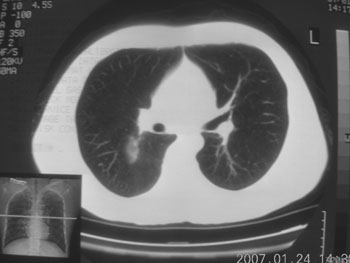

锁骨骨折复查,发现肺内高密度影,行ct检查。

男性,35岁,无任何感觉,无明显发热感冒病史。

病灶呈条片样变,边缘模糊,首先抗炎,然后复查。

右肺下叶背段斑片状阴影,边缘模糊,纵隔内未见肿大淋巴结,病人无发热及感冒史,要考虑浸润型肺结核,可结合ppd检查,或短期抗炎治疗复查。

右肺下叶背段长椭圆型病灶,边缘较规则,无明显分叶征、毛刺,远段未见阻塞征象,病灶较松散,纵隔窗明显小于肺窗,年龄35岁,支气管稍示变窄,纵隔内未见明显肿大淋巴结,这些都不支持肿瘤。病人无任何感觉,无明显发热感冒病史,首先考虑结核(也是结核好发部位),慢性炎症不能完全除外。